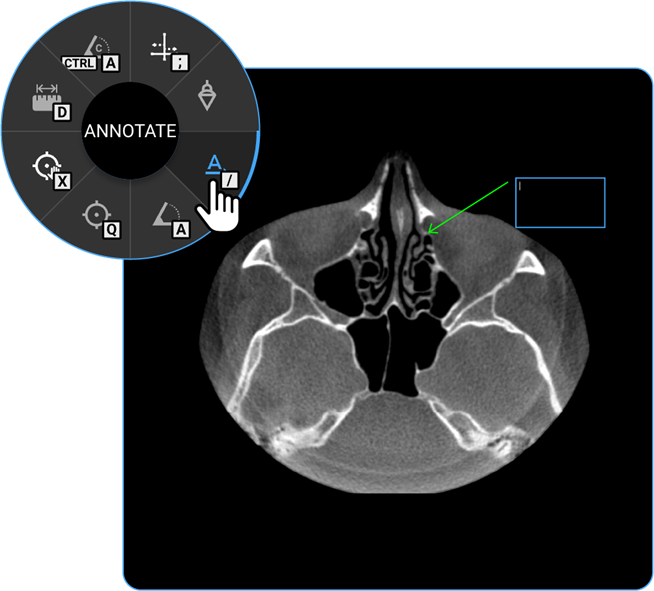

1. Annotate: Use the Annotate tool to add text or markers to the image for documentation or instructional purposes.

vai